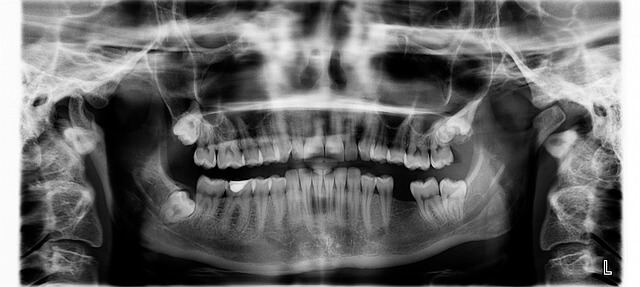

아말감이란 무엇인가?

아말감은 충치 치료 시 빠르게 굳는 금속 합성 재료로, 주로 수은, 은, 주석, 구리 등이 섞여 있습니다. 처음 듣기엔 ‘수은’이라는 단어 때문에 놀랍지만, 실제 치과용 아말감은 안정된 형태로 만들어져 체내로 흡수되지 않습니다. 쉽게 말해 고체 상태의 합금이기 때문에 입안에서 녹거나 증발하지 않아요.

저는 충치가 깊어 어금니 치료에 아말감을 썼는데, 치료 직후에는 약간 금속 맛이 났지만 며칠 지나니 전혀 느껴지지 않았습니다. 관리만 잘하면 10년 넘게 튼튼하게 유지된다고 하니, 내구성 측면에선 아직도 많은 치과에서 선호합니다.